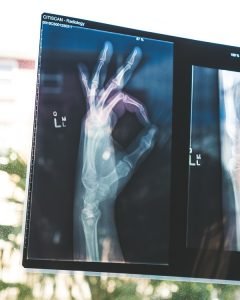

Bone mineral density is measured through a scan called a Dual-Energy X-ray Absorptiometry (DEXA). It can be used to measure the bone mineral density of the whole skeleton as well as specific sites. Approximately 21% of women aged 50–84 years are classified as having osteoporosis.2